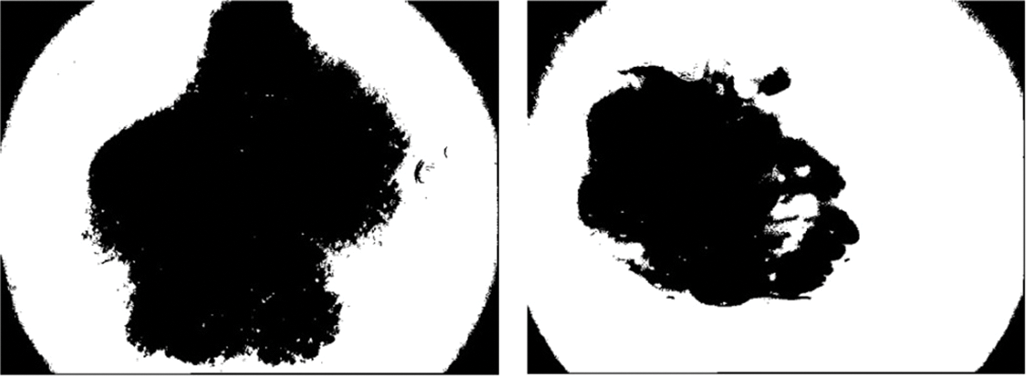

Ablation Study

We assembled the skin cancer pictures from the PH2 database. The resolution of pictures is 768 * 560 and is categorized into 3 classes Melanoma, Atypical Nevus, and Common nevi. The number of pictures in every class is 40, 80 and 80, respectively. A few sample pictures from the database are illustrated in Fig. 2. We employ the textural features of skin cancer photos to validate the precision and effectiveness of our suggested method. From GLCM numerous features are deployed for the skin cancer classification namely autocorrelation, Contrast, Correlation, Energy, Entropy, homogeneity, maximum probability, sum of squares, sum average, and sum variance. Each class of skin malignancy is differentiated by certain features. The algorithms for feature extraction withdraw distinctive features out of every class of skin cancer images. The GLCM acquires the RGB image initially and transforms it to a grayscale image, wherein the number of rows and columns matches the number of gray levels. The periodicity of a particular number of gray levels recurring at multiple points within an image is determined by GLCM. GLCM feature extraction exploits the spatial relationship among various combinations of pixels to map the gray level co-occurrence probabilities in distinct angular positions. The GLRLM is also employed to extract textural features. An algorithm for generating higher order statistical texture features is the GLRLM methodology. A line of pixels having an identical intensity value oriented in a particular direction is referred to as a gray level run. The gray level run length is computed by the amount of these pixels, and the run length value is the total number of occurrences. In this case, the number of adjacent pixels in the specified direction that have the same grey intensity can be referred to as the run length. 7 GLRLM features are withdrawn in our proposed method and the parameters are SRE, LRE, GLN, RLN, RP, LGLRE, and HGLRE. Also, we evaluated 8 statistical features. With the combination of 3 types of textural feature extraction, a total of 34 features are used in this work. A feature vector of 200 * 34, i.e., 200 images from the PH2 dataset and 34 textural features is made which is used to classify skin cancer into benign and malignant categories. The different segmentation techniques have been utilized and compared belonging to the categories: Thresholding based, cluster based, edge based, and region based. The segmentation results were compared with the reference images (ground truth) and the segmentation errors were evaluated by the 12 metrics described above. The results are illustrated in Figs. 18–20. Type 1: With an accuracy score of 90.00%, the Otsu (3 level) method is the best approach. The Otsu (2 level) and Sauvola have the best SE rate, which is 97.50%. The Binarized Sauvola achieves the best SP rate of 82.50%. The Binarized Sauvola achieves the best PPV rate of 91.30% (benign) and 82.5% (malignant). The Binarized Sauvola achieves the best FDR rate of 8.8% (benign) and 17.5% (malignant). The Otsu (2 level) yields the best NPV rate of 91.30%. The Otsu (2 level) yields the best FNR rate of 2.50%. The Binarized Sauvola achieves the highest FPR (17.55%). The Binarized Sauvola achieves the best BA rate of 86.80%. The Otsu (3 level) achieves the best F1 rate of 92.70%. The Otsu (3 level) achieves the best MCC rate of 77.15%. The Otsu (2 level) and Sauvola have the best AUC rate, which is 97.50%. The Binarized Sauvola achieves the best SE rate of 93.50% as shown in Table 3. Table 4 shows the median of the segmentation scores for each method.